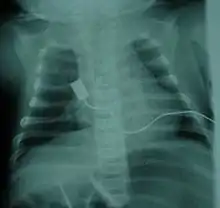

The symptoms vary depending on the SMA type,[4] below are most common in the severe SMA type 0/I:

- Bell-shaped torso (caused by using only abdominal muscles for respiration) in severe SMA type 1[7]

The respiratory system is the most common system to be affected and the complications are the leading cause of death in SMA types 0/1 and 2. SMA type 3 can have similar respiratory problems, but it is more rare.[23] The complications that arise are due to weakened intercostal muscles because of the lack of stimulation from the nerve. The diaphragm is less affected than the intercostal muscles.[23] Once weakened, the muscles never fully recover the same functional capacity to help in breathing and coughing as well as other functions. Therefore, breathing is more difficult and pose a risk of not getting enough oxygen/shallow breathing and insufficient clearance of airway secretions[32]: 378 . Swallowing muscles can be affected, leading to aspiration coupled with a poor coughing mechanism increases the likelihood of infection/pneumonia.[55][56] Mobilizing and clearing secretions involve manual or mechanical chest physiotherapy with postural drainage, and manual or mechanical cough assistance device. To assist in breathing, non-invasive ventilation (BiPAP) is frequently used and tracheostomy may be sometimes performed in more severe cases[57]